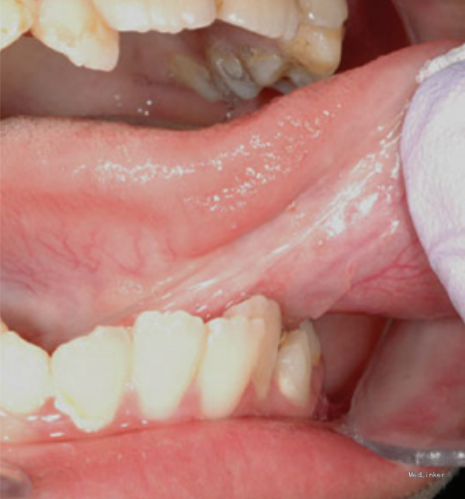

患者八岁,发现舌部有一逐渐生长的肿物一个月,没有其他不适。患者患有共济失调 - 毛细血管扩张症。

检查发现舌下有一隆起,约1.2*1cm大小,未影响舌功能和运动,唾液分泌正常,周围淋巴结无肿大。 影像检查显示右舌有一不规则圆形肿物,边界不清。